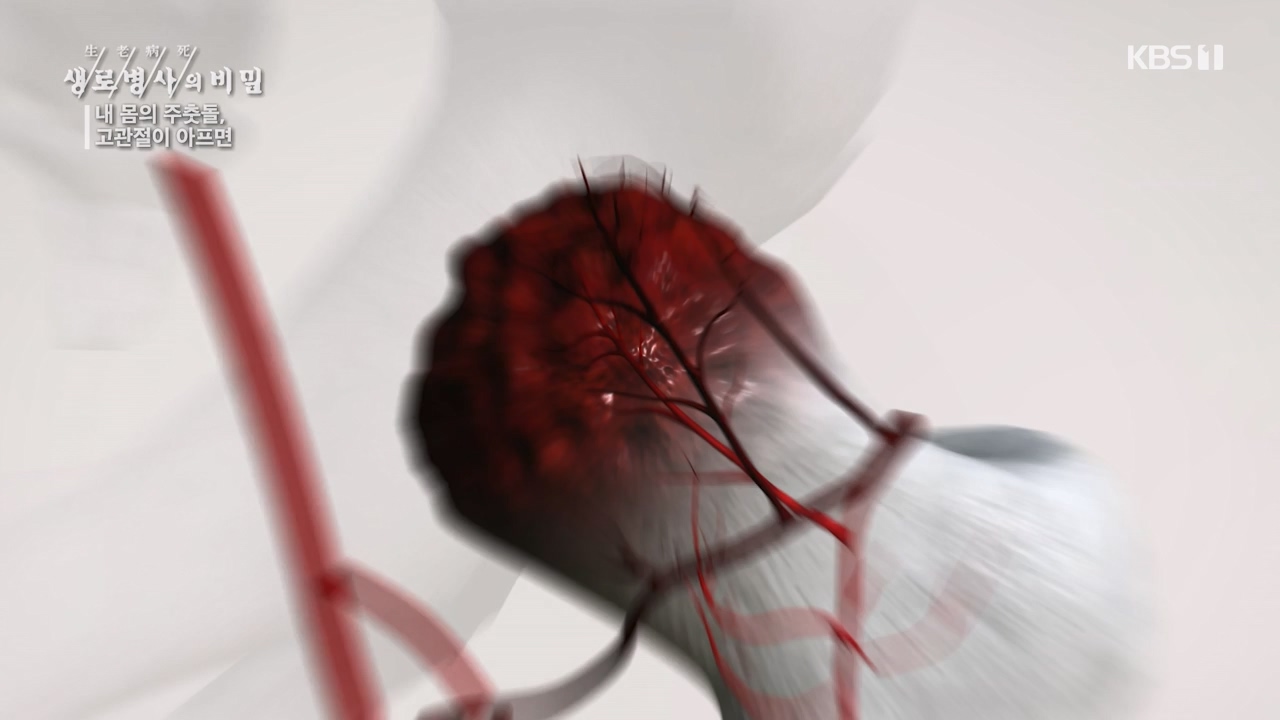

[박은철 기자] 앉고 서고 걷고 달리는 등 우리가 움직이는 순간마다 쉼 없이 일하는 관절이 있다. 엉덩이 관절이라고도 불리는 '고관절'은 상체와...